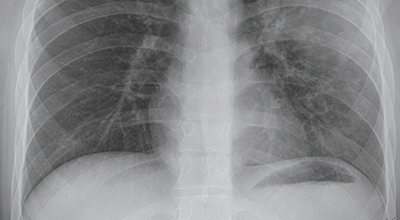

4. 폐렴 진단: 어떻게 폐렴을 확인할 수 있을까요?

폐렴은 증상만으로는 정확하게 진단하기 어려우므로, 다음과 같은 검사를 통해 진단합니다.

- 흉부 X선 촬영: 폐의 염증 부위를 확인하는 가장 기본적인 검사입니다.